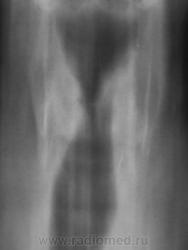

Пол пациента: Мужской пол Тип патологии: Злокачественное новообразование Область исследования: Грудная клетка и верхние дыхательные пути Методы исследования: Rg Пациент направлен на томографию гортани. https://radiomed.ru/sites/default/files/styles/case_slider_image/public/user/12/2.pb120004_0.jpg?itok=4--aFyQT https://radiomed.ru/sites/default/files/styles/case_slider_image/public/user/12/3.pb120005_0.jpg?itok=1jADholg https://radiomed.ru/sites/default/files/styles/case_slider_image/public/user/12/4.pb120006_0.jpg?itok=VTi_5Yha ID:8786